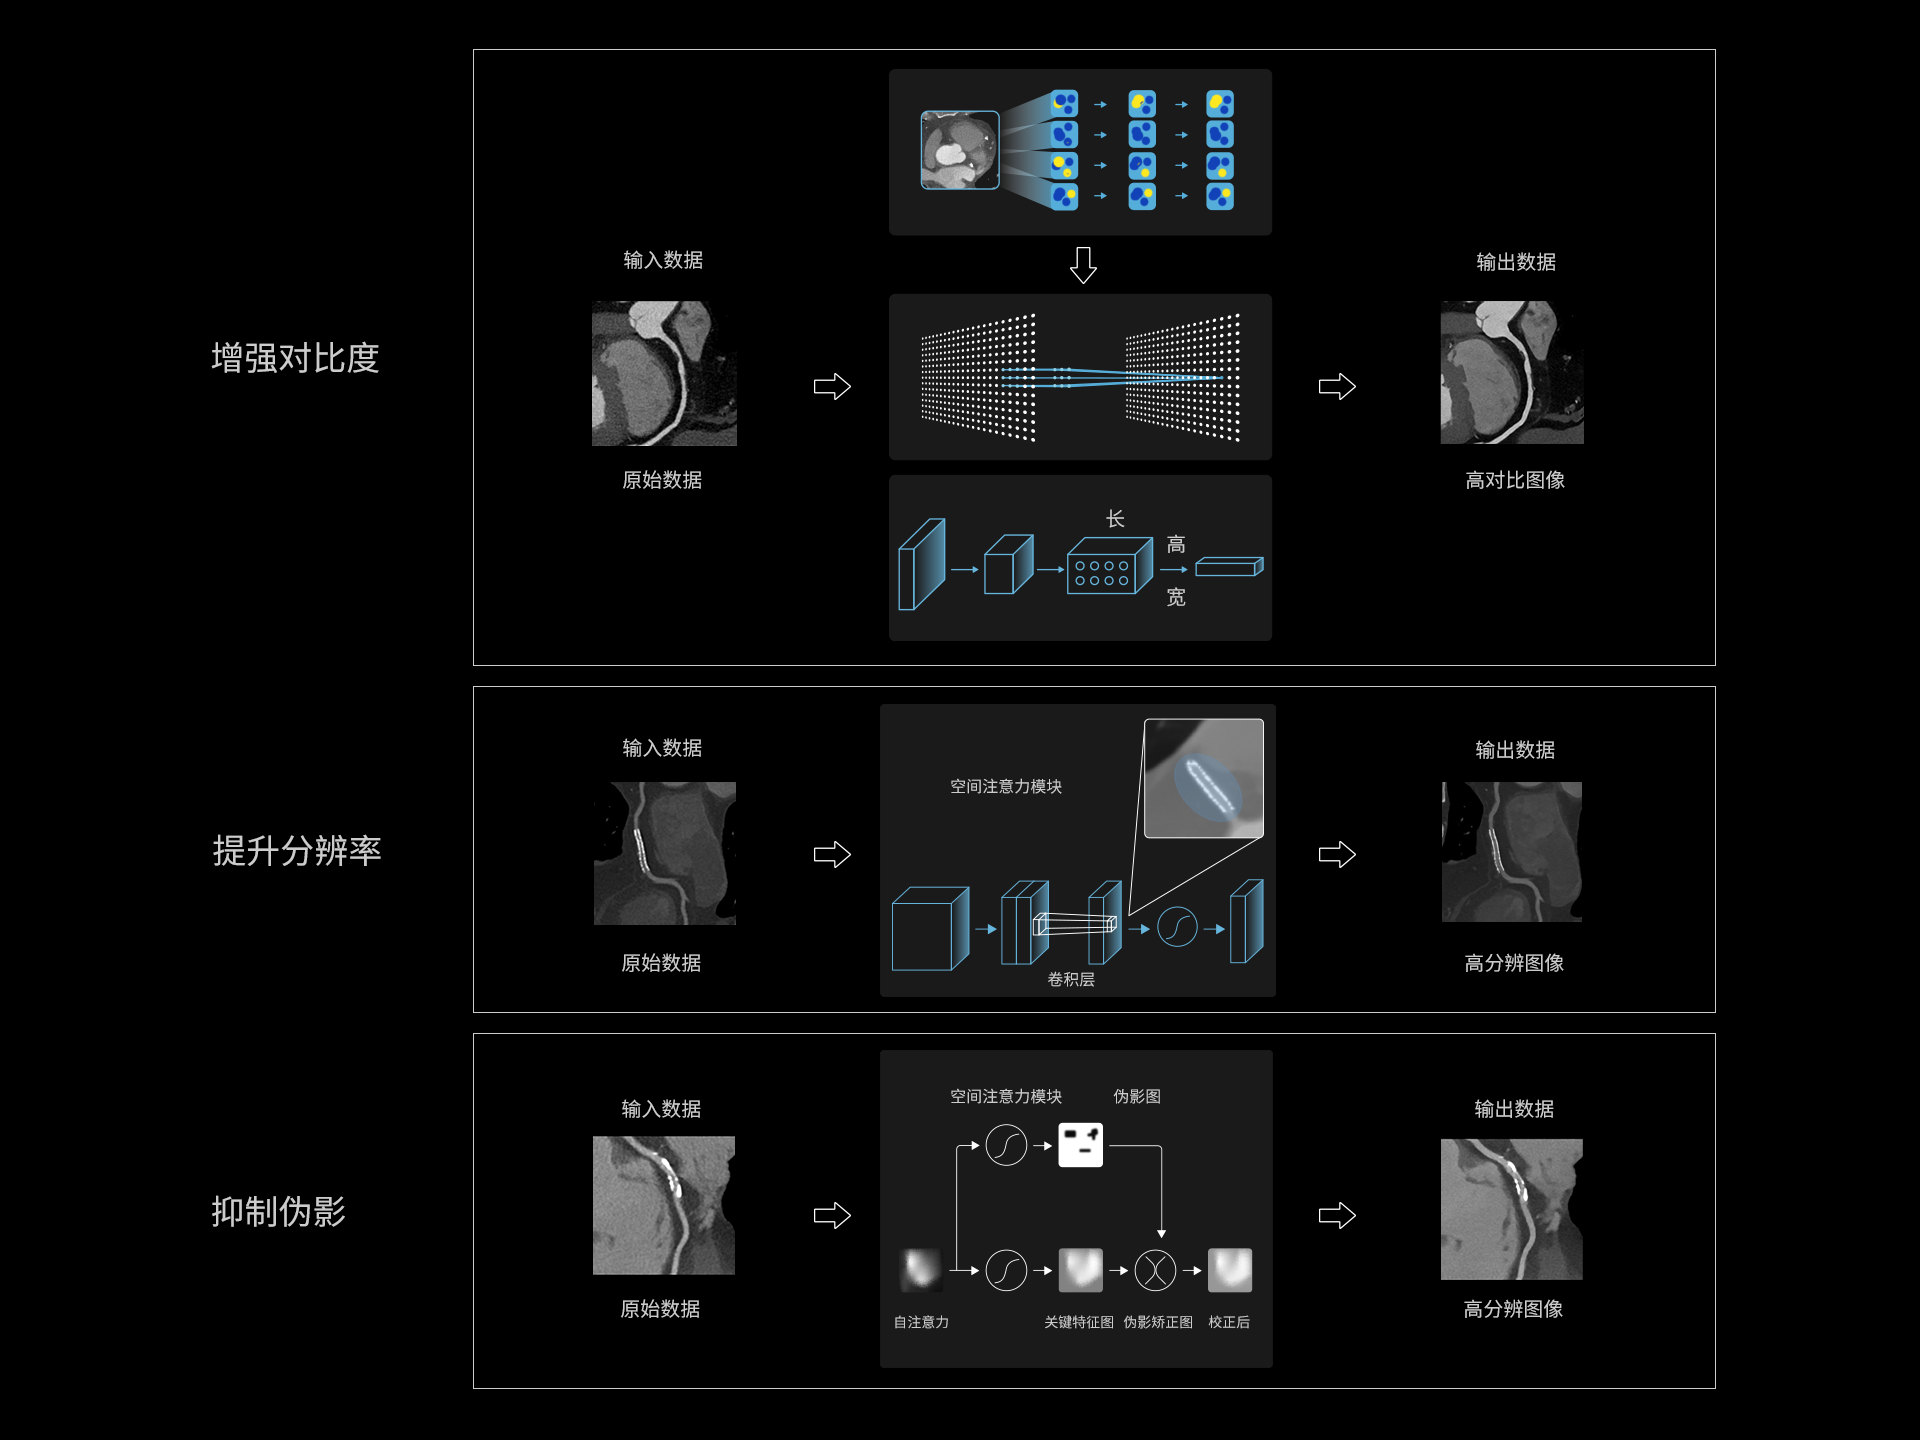

针对心脏重建算法精心研发,利用深度学习技术显著增强图像分辨率、消除伪影干扰,同时有效降低辐射剂量与噪声,维持图像纹理的自然与真实。

低对比度分辨率提升99%*,利于斑块、心肌、瓣膜显示

空间分辨率提升72%*,利于钙化斑块、支架显示

抑制高密度物质条状、晕状伪影,管腔狭窄程度评估更准确

精准洞察患者对安全的需求、及影像科面对的繁重工作,uCT Atlas Pro将尖端的深度学习技术融入图像重建环节,实现图像质量的全面提升,也可大幅降低CT检查的辐射剂量。创新的智慧感知技术,为影像学领域的发展注入了新鲜活力与强劲动力!